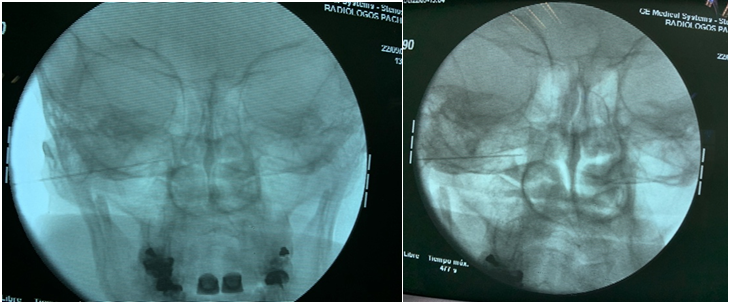

SPG blockade was proposed as a therapeutic option, with prior informed consent. In the operating room and placed in the supine position, the face was prepared and covered in a sterile manner. Superficial sedation was used under standard ASA monitoring. With the head in a neutral position to expose the infracygomatic region on the affected side, fluoroscopy was used to navigate the pterygopalatine ganglion with a 20G (90mm) needle. First, the needle is directed medially in coaxial view until it passes the zygomatic arch (very superficial). Then, is slightly redirected cephalad into the pterygopalatine fossa under intermittent fluoroscopy (Figure 1). In a posteroanterior (PA) view, the needle should be on the lateral wall of the nostril at the level of the middle turbinate (Figure 2).

Figure 1 Lateral image with focus on the pterygopalatine fossae. The needle is placed in coaxial view toward the fossa, beyond the zygomatic arch, then redirected slightly cranially.